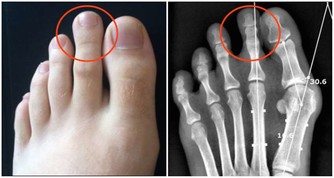

1、腐腥臭是肺癌

當患上肺部疾病時比如肺部感染肺炎、氣管炎、肺癌都會引起口臭,主要是因為患者的肺部積攢了大量粘液所引起的口臭。肺膿腫的患者一般會伴隨腐酸性口臭味,同時也會伴有膿性痰以及發燒,只有去醫院做胸片檢查才能夠確診。支氣管擴張以及肺結核患者會出現血腥味的口臭,晚期肺癌患者會有腐腥口臭味。